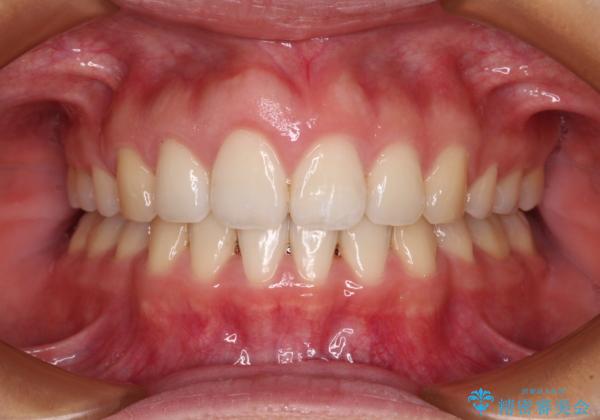

4本の歯を抜歯したことで、飛び出していた口元が引っ込み、横顔が大きく改善されました。

咬み合わせが悪化することのないようにスペースを閉じていくことができ、比較的スムーズに治療を進めることができました。